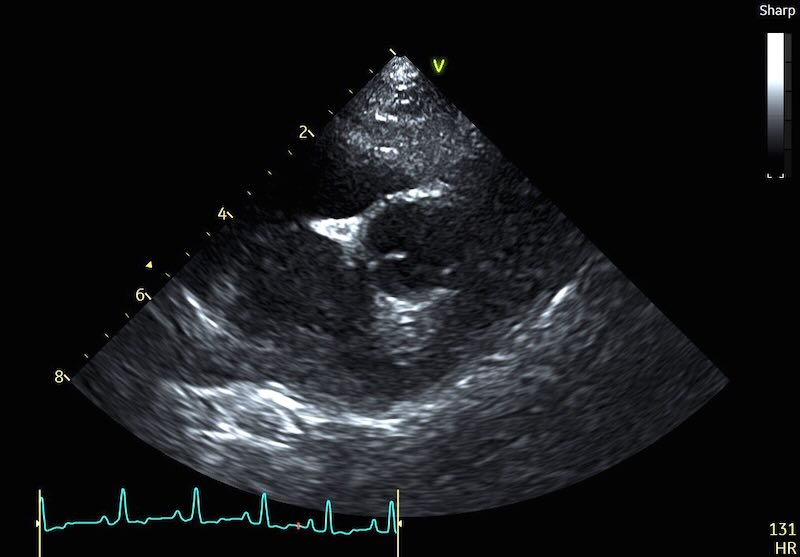

Here are 2 examples of a normal LA with a pulmonary vein, and a very enlarged LA also having pulmonary vein issues:

The Clinical Workaround: If you see a vein entering the atrium, do not measure into the vessel. There are multiple described approaches for coping with this, and as yet no consensus on the best approach:

- Option 1: “approximate” the atrial border by connecting the visible edges of the atrium with an imaginary curved line that follows the natural contour of the chamber. If the dropout is so severe that you are guessing, it is time to move to a different view.

- Option 2: Angle your measure to the little ‘bump’ that sits just to the right of the vein.

- Option 3: Angle your measure to the wall where it first becomes visible to the left of the vein

Personally, I’m a fan of option 2. But set guidelines if published will maybe solve this debate for good…